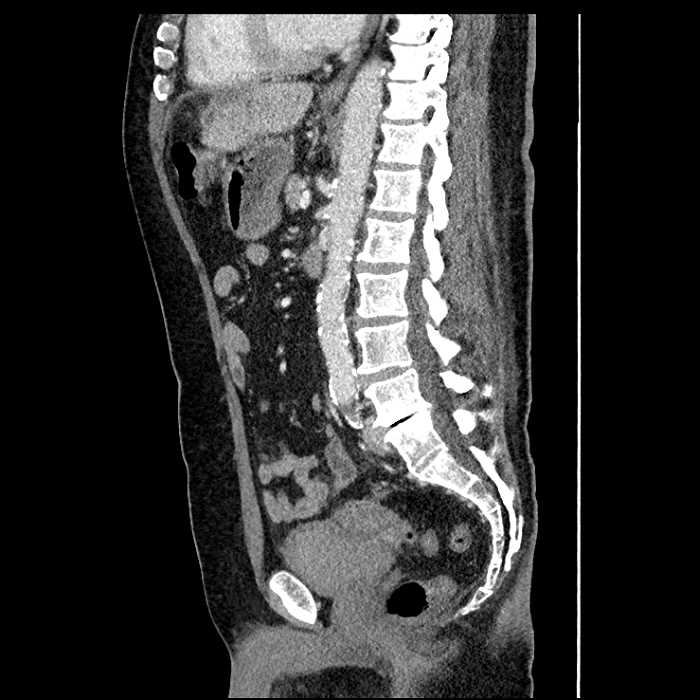

Age: 63

Sex: Male

Indication: Abdominal pain

• Mild mural thickening of a segment of the sigmoid colon with adjacent fat stranding and a 1.5 cm fluid and gas collection along the tip of an inflamed diverticulum

• Loss of the normal fat plane between this collection and adjacent loops of small bowel, which demonstrate mural thickening

• No bowel obstruction

Acute sigmoid diverticulitis complicated by a small contained perforation and a large abscess in the right hepatic lobe. Additional small subcapsular abscesses along the anterior margin of the left hepatic lobe.

Additionally, loss of the normal fat plane between the peridiverticular collection and adjacent thickened loops of small bowel raises the potential for an enterocolonic fistula.

Hepatic abscess showing the double target sign with low density internally surrounded by a thin inner enhancing rim (red arrow) and ill-defined outer low density rim (yellow arrow). Blue arrow indicates an internal septation. Red arrows: additional smaller subcapsular abscesses. Red arrow: focal contained perforation associated with diverticulitis.